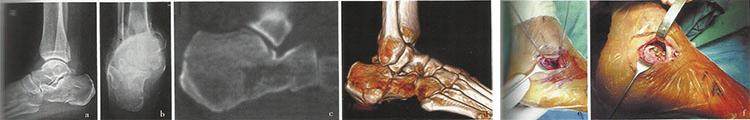

3.5/4.0跟骨锁定板

3.5/4.0跟骨锁定板 5孔 分左右

3.5/4.0跟骨锁定板 12孔 大、小 分左右

微创跟骨锁定板